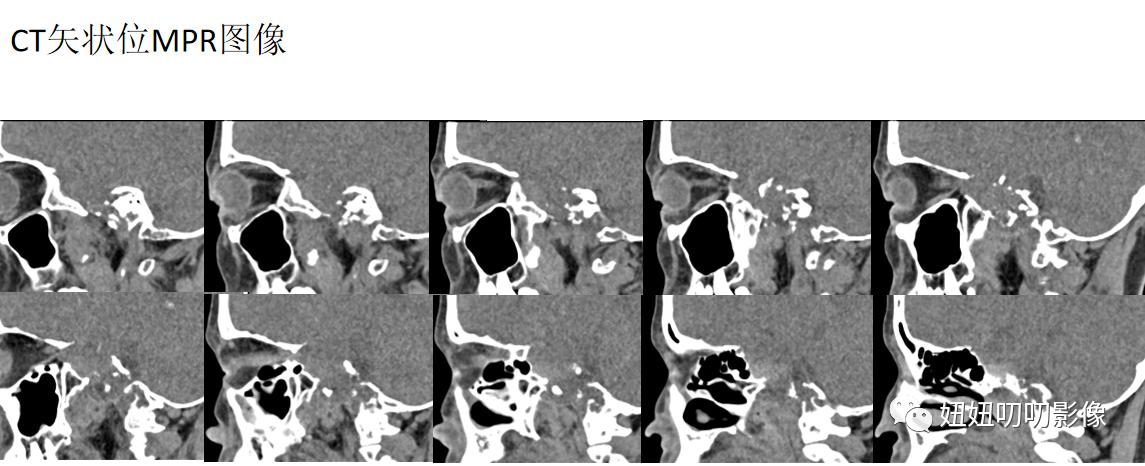

CT:鞍区及左侧岩尖区见不规则形等低密度灶,其内密度不均,可见斑点状致密影,斜坡、海绵窦、颞骨岩部骨质破坏,边界欠清,大小3.6x3.7x4.4m,增强扫描呈轻度不均匀强化,脑桥前缘、垂体、视交叉、左侧颞叶受压移位,左侧颈内动脉、大脑中动脉受压、迂曲增宽。

A:你看矢状位CT,这个钙化,迂曲状,这么多钙化,还是考虑软骨源性肿瘤,年纪50多,也可以了,不知道有没有价值,总感觉T1巨低,和动脉瘤都差不多了。